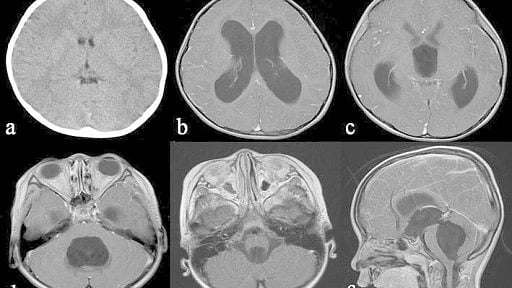

Hydrocephalus is prevalent worldwide and can affect people of any age.  Ishi Y, Asaoka K, Kobayashi H, Motegi H, Sugiyama T, Yokoyama Y, Echizenya S, Itamoto K, CC BY 4.0, via Wikimedia Commons

Hydrocephalus is prevalent worldwide and can affect people of any age. According to the Hydrocephalus Association, one million Americans suffer from the condition and some 25 million worldwide. The most common medical conditions that can lead to hydrocephalus are children who are born with hydrocephalus or develop it from brain hemorrhage of prematurity, people with head trauma, aneurysms, strokes or tumors, and elderly who can develop normal pressure hydrocephalus. Some people with hydrocephalus have a severe build-up of pressure in the brain that can be life-threatening. Others who are elderly can have hydrocephalus that causes difficulty with walking, bladder control and memory loss.